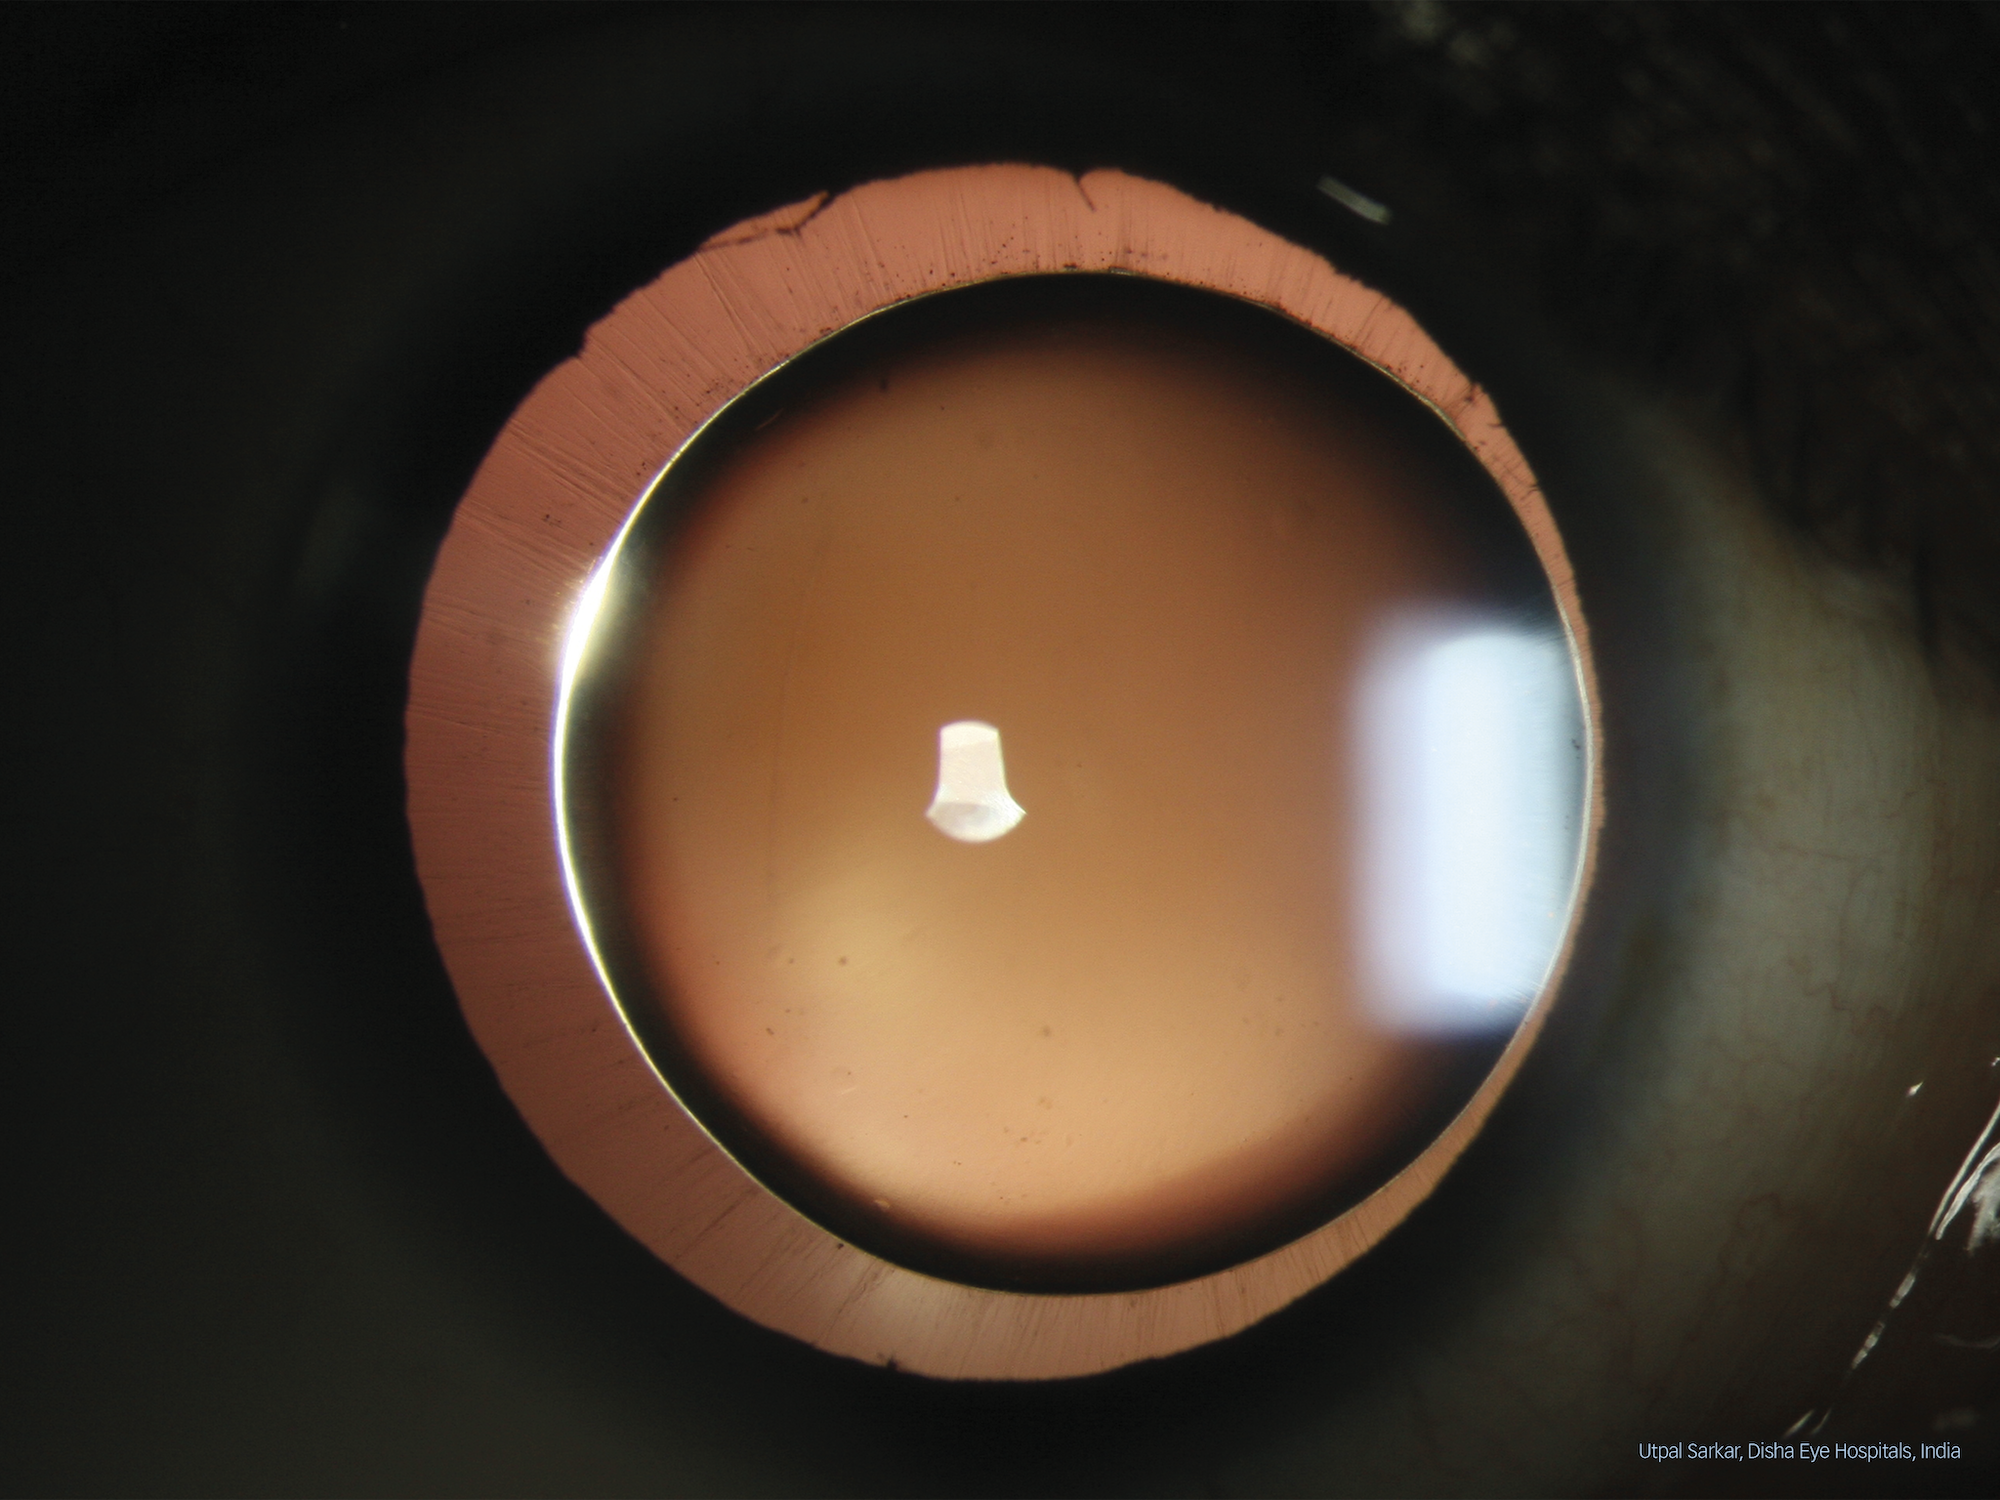

Utpal Sarkar’s winning image

A slit lamp image of a case of spherophakia has won the Haag-Streit Slit Lamp Imaging Competition 2022.

The first prize, a Sony Alpha 7 IV Kit, was awarded to Utpal Sarkar from Disha Eye Hospitals Barrackpore in Kolkata, India. His winning image, taken with a Haag-Streit BX 900 Imaging System, shows a case of spherophakia and excelled in all three of the winning criteria: image quality, technical execution and disease interest. The jury said they were especially impressed by “the ciliary zonule being in full focus over nearly the entire 360° of the eye”.